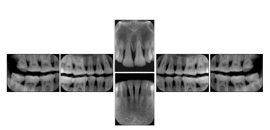

2. A patient requests cosmetic surgery to enhance their facial appearance. The case requires consultation between an orthodontist in New York and an oral surgeon in California. The cephalometric series of 2D projections constructed from the volumetric CT data that is used for the discussion is arranged by a Structured Display for transfer between the two practitioners.

Cephalometric Series Structured Display

Figure OO-2. Cephalometric Series Structured Display